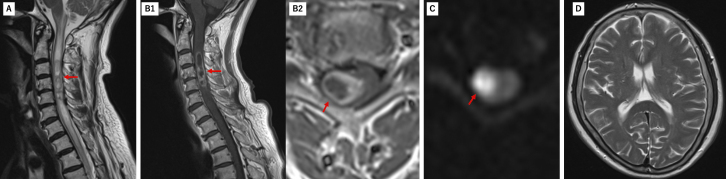

髓内脊髓脓肿很少引起意识受损而不引起颅内感染。我们报告的情况下,65岁的妇女谁提出颈部疼痛和右上肢无力。入院三天内,她的意识迅速恶化。最初的磁共振成像显示右侧C4-C5髓内病变,周围水肿延伸至脑干。脑成像未见异常。初步诊断为脊髓肿瘤。随访影像学显示病灶扩大伴环形强化。患者随后出现意识受损和四肢瘫痪。急诊手术发现并排出脊髓脓肿,培养物生长α-溶血性链球菌。手术后病人的意识恢复得很快。入院时发现先前未确诊的2型糖尿病。经广泛调查,未发现明显传染源。氨苄西林抗生素治疗持续1个月。两个月后的影像学显示脓肿完全消退。患者康复后恢复独立行走能力,仅残留轻微右臂无力。随访10年未见复发。本病例表明,颈脊髓脓肿可通过脑干水肿引起意识受损,而不发生颅内感染。早期手术干预配合适当的抗生素治疗可获得良好的结果。

Intramedullary spinal cord abscesses rarely cause impaired consciousness without intracranial infection. We report the case of a 65-year-old woman who presented with neck pain and right upper limb weakness. She developed rapidly progressive impaired consciousness within three days of admission. Initial magnetic resonance imaging revealed a right-sided intramedullary lesion at C4-C5 with surrounding edema extending to the brainstem. Brain imaging showed no abnormalities. An initial diagnosis of a spinal cord tumor was made. Follow-up imaging demonstrated lesion expansion with ring enhancement. The patient subsequently developed impaired consciousness and quadriplegia. Emergency surgery revealed and drained a spinal cord abscess, with cultures growing α-hemolytic Streptococcus. The patient's consciousness improved quickly after surgery. Previously undiagnosed type 2 diabetes was identified during admission. Despite extensive investigation, no obvious source of infection was found. Antibiotic therapy with ampicillin was continued for one month. Imaging at two months showed complete resolution of the abscess. The patient regained independent walking ability after rehabilitation, with only slight residual right arm weakness. No recurrence was observed during ten years of follow-up. This case demonstrates that a cervical spinal cord abscess can cause impaired consciousness through brainstem edema without intracranial infection. Early surgical intervention combined with appropriate antibiotics may lead to favorable outcomes.